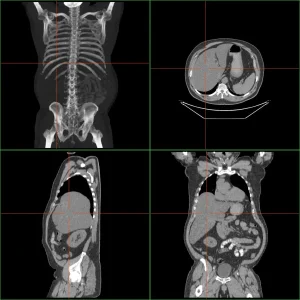

Além dos sintomas, exames físicos e exames de imagem como ultrassonografia (US), tomografia computadorizada (TC) ou ressonância magnética (RM), bem como a angiografia, são utilizados para diagnosticar a hepatomegalia.

Também pode ser realizada uma biópsia hepática, geralmente guiada por ultrassom ou tomografia, permitindo a avaliação microscópica do tecido danificado.